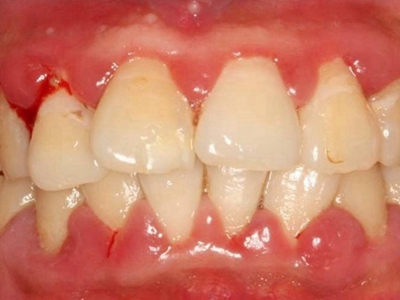

牙龈炎是发生于牙龈组织的炎症,患者可出现牙龈出血伴肿胀、发红、正常形态改变和偶尔不适等症状。本病主要由口腔卫生状况差导致,包括口腔不洁、牙菌斑等,诊断依据临床检查,治疗包括专业牙齿清洁和加强家庭口腔卫生。

牙龈炎可先引起牙齿与牙龈之间的沟(龈沟)加深,然后牙龈充血,炎症围绕一个或多个牙齿,伴牙龈乳头肿胀和易出血。一般无痛,可自行消退,也可维持轻度炎症数年。